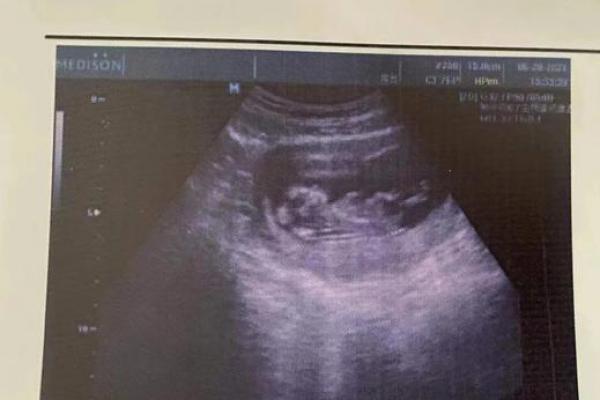

做B超检查时,发现没有胎心,这是不是胎死腹中了呢?胎心搏动是评价胎儿在 *** 内生长发育的重要指标,但没有胎心,不一定是死胎。

B超检查的话,会出现胎芽,胎儿形态不整,无胎心搏动,或表现为空囊。在医学临床上属于流产、或死胎范畴。原因主要有染色体异常、遗传基因存在缺陷、 *** 腔畸形、男方 *** 质量不好等等。

一般情况下,B超检查中没有看到胎心、胎芽,有这么2种原因:受孕晚 对于一部分的孕妇来说,因为受孕晚,就会导致胎心、胎芽出现的晚,这类情况需要多次、动态观察。